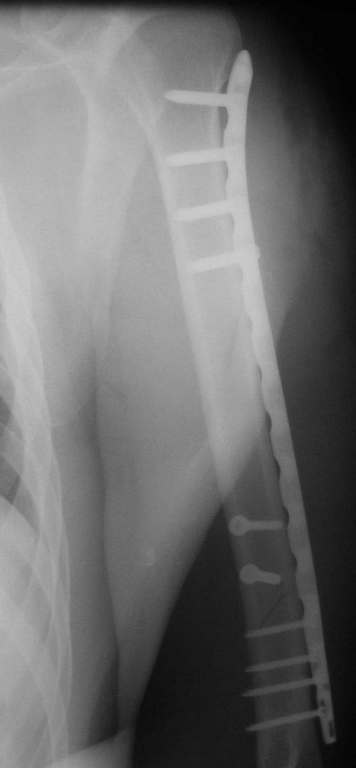

Позвольте привести пример из собственной московской практики в поддержку тактики, приведенной в данном примере. Пациент переведен из одной из московских клиник на 3 сутки после сквозного огнестрельного ранения плеча(пистолет)с ушитыми узловыми швами и дренированными резиновым выпускником ранами на внутренней поверхности плеча с умеренным серозногнойным отделяемым и похожей раной на задненаружной поверхности грудной клетки (пуля прошла через плечо и остановилась в мышцах спины). Также имелись реактивный локтевой бурсит и нейропатия локтевого нерва. При поступлении были сняты швы, начата антибиотикотерапия. Через сутки после травмы пациент прооперирован: выполнена повторная хирургическая обработка ран плеча и грудной клетки. Через отдельные доступы на наружной поверхности плеча произведен минимально инвазивный остеосинтез плечевой кости блокируемой метадиафизарной пластиной. Пациент выписан на 4 сутки после операции. Дальнейшее течение гладкое, все раны зажили первичным натяжением. Еще раз пациент был госпитализирован через 4 месяца после операции с переломом этого же плеча на границе средней и дистальной третей: коллеги по криминальному ремеслу применили к нему слишком жесткие меры убеждения. Выполнен остеосинтез путем замены и добавления винтов в дистальной части пластины. Госпитализация 2 суток. К сожалению, последние снимки не сохранились.